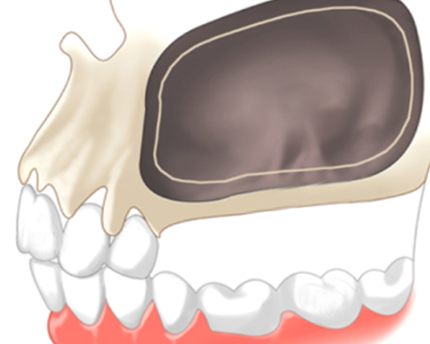

상악동은 머리뼈 중 코 옆에 빈공간을 말합니다.

이부분에 잇몸뼈가 부족할 경우 상악동거상술이 필요합니다.

상악동은 코 뼈 옆 빈 공간을 말하는데 상악동이 빌 경우 임플란트를 단단히 지지할 수 없어 상악동을 들어 올려 뼈를 이식하는 것을 상악동거상술이라 합니다.